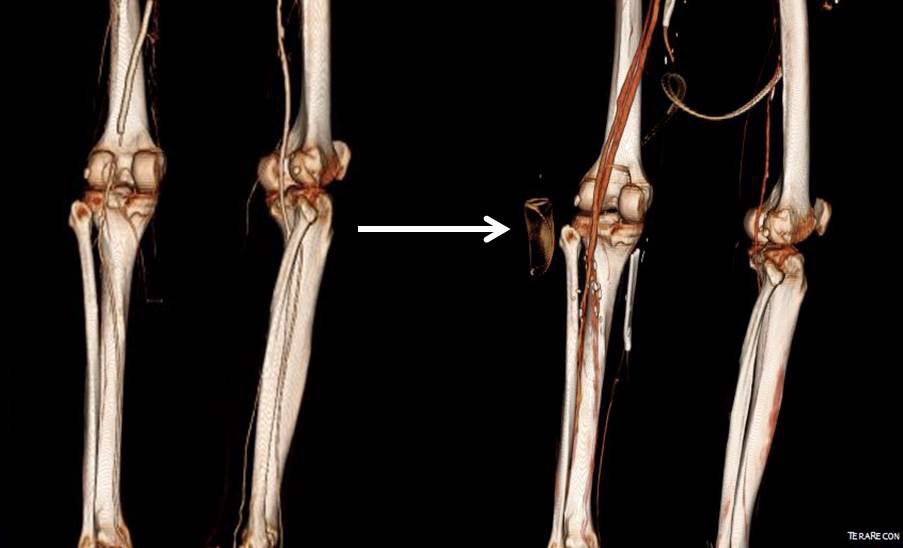

Let me show you one of the first cases I did after returning to Cleveland. I am now practicing at Fairview and Avon Hospitals, premier flagship hospitals in the Cleveland Clinic fleet, on Cleveland’s west side, and a patient arrived while I was on call with sudden onset of pain in his leg from a lack of blood flow. He had occlusive atherosclerotic plaque extending from his external iliac artery to the above knee popliteal artery causing ischemic rest pain.

I contacted LeMaitre Vascular and got in touch with your representative, L. Fisher, who promptly sent the Moll Ring Cutters I needed to perform a remote endarterectomy of the patient’s occlusive external iliac and superficial femoral artery plaque. The technical details of remote endarterectomy are have been covered in my blog (https://vascsurg.me/?s=endore), but in the end, through a 7cm incision in the groin (don’t believe the hype, this is minimally invasive), I restored his arteries to their original open condition. Shown below are the results. It was with great sadness that I heard that the LeMaitre Vascular equipment being sent were the last of the stock available in North America. The patient did very well, with the operation completed well before lunch, and is recovering rapidly from his small wound and big rescue. He gets to walk out of the hospital on two legs, but also with the surety that he avoided a major bypass operation, and avoided the short term gains of stenting from the aorta to the profunda -more peel packs and landfill items and a dubious long term durability. Hey, I even used a XenoSure patch on the common femoral.